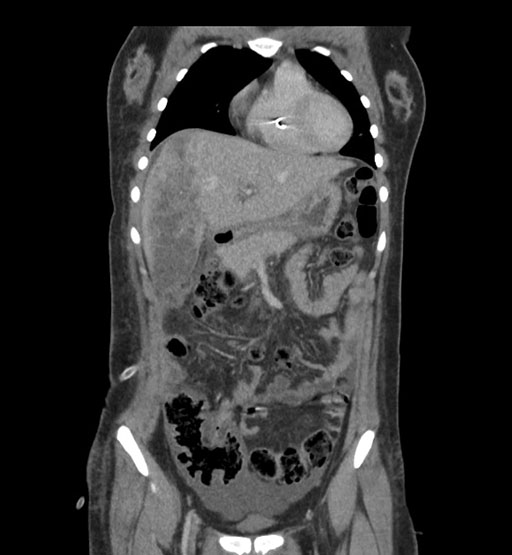

Coronal Arterial

Coronal Venous